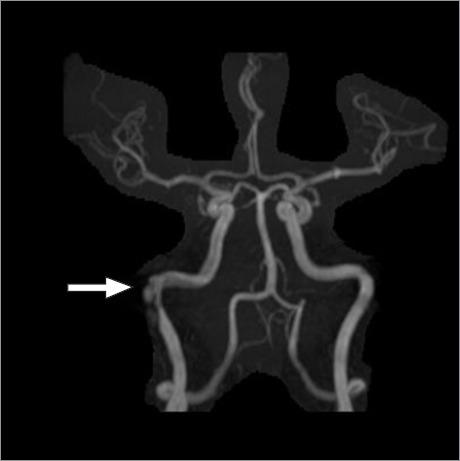

活动期 COVID-19 患者的自发性右岩骨内颈动脉夹层。

Spontaneous Right Intrapetrous Internal Carotid Dissection in a Patient With Active COVID-19.

Spontaneous cervical artery dissection, a nontraumatic tear in the wall of an internal carotid or vertebral artery, is a common cause of stroke, particularly in patients younger than 40 years of age; however, petrous internal carotid artery dissection is extremely rare. This case report describes a 50-year-old woman who had a spontaneous intrapetrous internal carotid dissection thought to be secondary to active SARS-CoV-2 infection; the dissection was treated successfully with a flow-diverter stent.

摘要

自发性颈内动脉夹层,即颈内动脉或椎动脉壁的非外伤性撕裂,是中风的一个常见原因,特别是在 40 岁以下的患者中;然而,岩骨内颈动脉夹层极为罕见。本病例报告描述了一位 50 岁女性,她患有自发性岩骨内颈动脉夹层,据认为是继发于活动性严重急性呼吸综合征冠状病毒 2 感染;该夹层通过使用血流导向支架成功治疗。